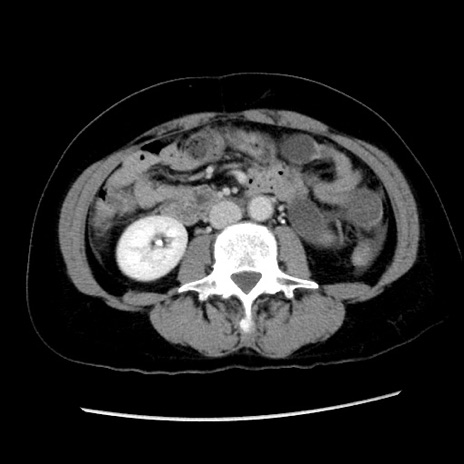

症例10(横断像)

【症例】 50歳代女性

【主訴】 腹痛

【現病歴】前日生レバーを食べた。今朝に排便あり。 昼前に突然発症の腹痛を生じ、当院救急外来を受診した。

【身体所見】 意識清明、腹部:平坦、軟、下腹部やや左を中心に圧痛・反跳痛あり、筋性防御あり